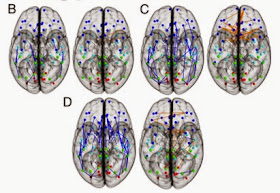

| Top showing greater intra-hemisphere connections in the male brain and the bottom showing more inter-hemisphere connections in the female brain. |

| Analysis on the child (B), adolescent (C), and young adult (D) groups is shown. Intra-hemispheric connections are shown in blue, and inter-hemispheric connections are shown in orange. |

These physiological structures suggests that the male brain is "structured to facilitate connectivity between perception and coordinated action," whereas female brains are organized to "facilitate communication between analytical and intuitive processing modes"(5). While males typically have a larger body mass than women, they also have "larger crania ... and a higher percentage of white matter" that contains myelinated neural axons and cerebrospinal fluid (1). Women on the other hand have a higher percentage of gray matter that is made up of neural bodies(1). A review found that "In men, IQ correlates with gray matter volume in the frontal and parietal lobes; whereas in women, IQ correlates with gray matter volume in the frontal lobe and Broca’s area,[a region of the frontal lobe associated with speech production] ... suggesting that men and women use different brain areas to achieve a similar IQ"(1).

Interestingly, this physiological study was also paired with a behavioral study on the same 949 children and found pronounced sex differences. "[F]emales outperform males on attention, word and face memory, and social cognition tests and males perform better on spatial processing and motor and sensorimotor speed"(5). So it appears there is a physiological reason for the differences between men and women.